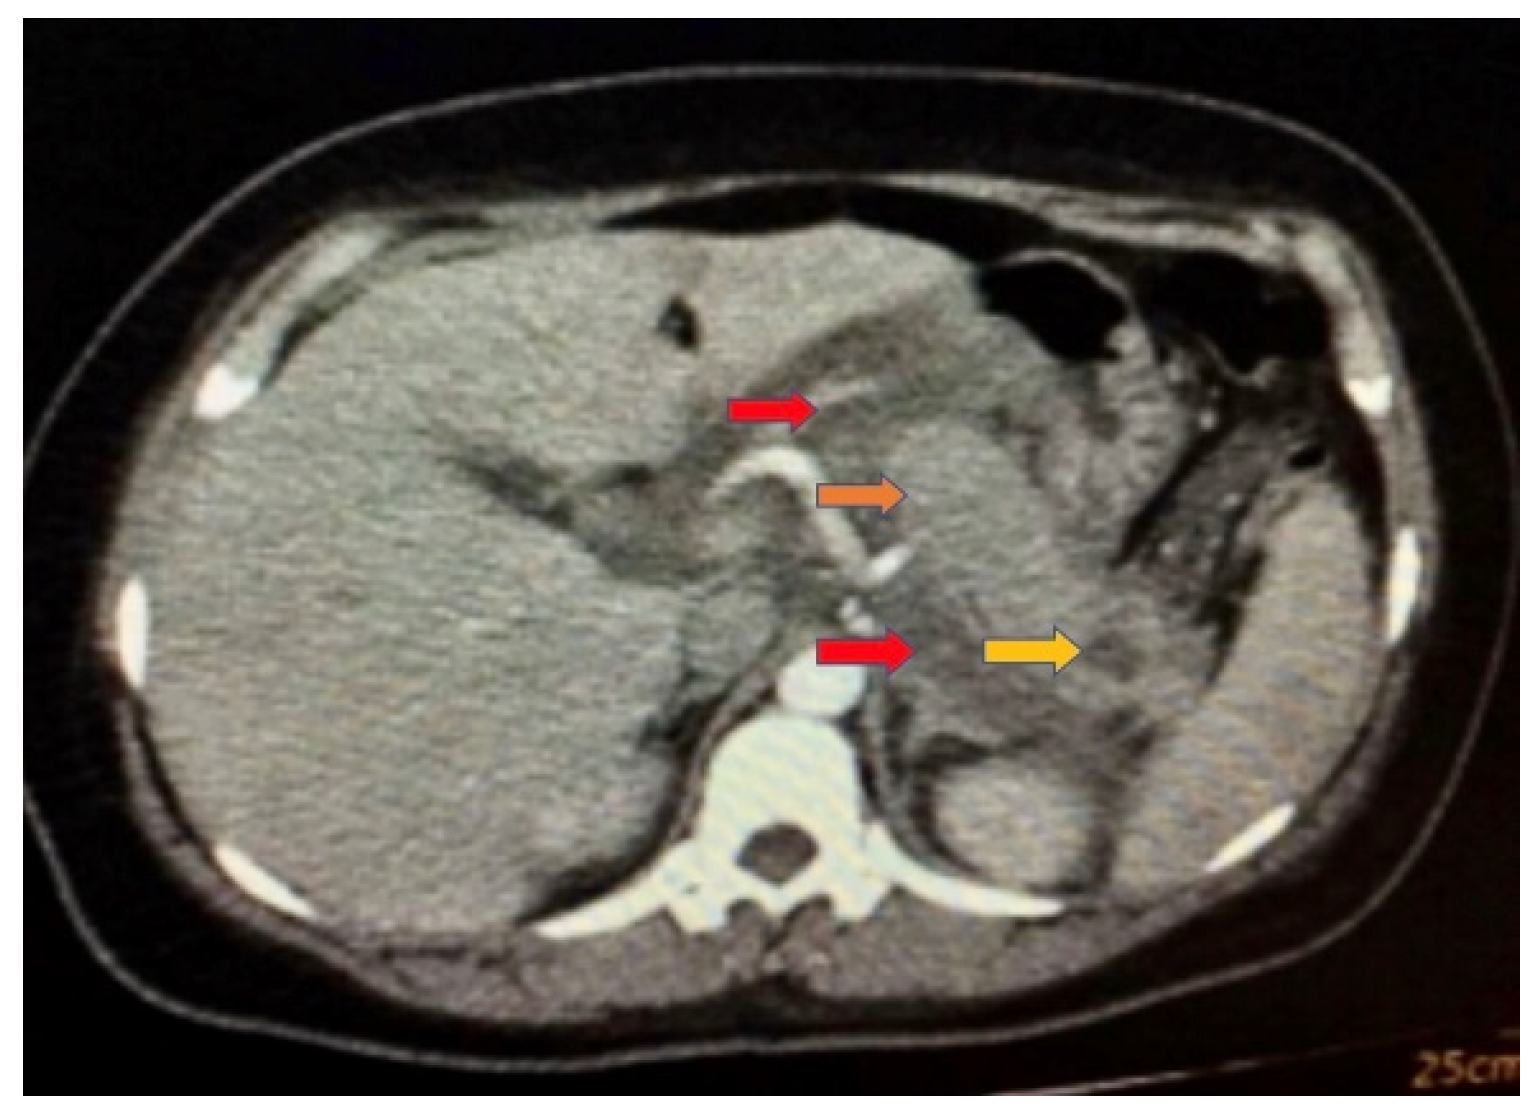

Figure 1. Simple Abdominal Tomography 72 h after admission: enlarged heterogeneous pancreas (orange arrow), with significant edema of peripancreatic fat (red arrows), and presence of a hypodense lesion in the pancreatic tail with irregular edges 16 × 9 mm with 5% necrotic area associated with peripancreatic collections (yellow arrow), cataloged as Balthazar D.

The patient was diagnosed and managed in the Intensive Care Unit (ICU) of Pablo Arturo Suárez Hospital in Quito, Ecuador, in 2022. On admission, the patient required endotracheal intubation, invasive mechanical ventilation, and vasopressor support due to hemodynamic instability. The diagnosis of acute pancreatitis was established based on the American Gastroenterological Association (AGA) criteria, which require the presence of at least two of the following three parameters: (1) characteristic epigastric pain, (2) serum amylase and/or lipase levels elevated to more than three times the upper limit of normal, and (3) radiological findings consistent with pancreatitis on cross-sectional imaging. The patient presented with severe abdominal pain, an amylase level of 480 mg/dL, and a lipase level of 984 mg/dL. Contrast-enhanced computed tomography (CT) of the abdomen, performed within 72 h of admission, revealed pancreatic enlargement with heterogeneous attenuation, marked peripancreatic fat stranding, and a hypodense lesion with irregular margins measuring 16 × 9 mm in the pancreatic tail, comprising approximately 5% necrotic area, along with peripancreatic fluid collections. The findings were consistent with Balthazar grade D pancreatitis. Given the clinical presentation and severe hypertriglyceridemia, a diagnostic workup for familial chylomicronemia syndrome (FCS) was performed in accordance with established diagnostic algorithms [12]. The diagnosis was further supported by the Diagnostic Index of Suspicion for FCS (see Table 1).

On day 2, she had hypercholesterolemia and hypertriglyceridemia, as well as normal high-density and low-density lipoproteins. On day 3, a decrease in hemoglobin was observed, although lipid values remained high. On day 7, she presented an exacerbation of pain, abdominal distension, and increased conjunctival jaundice. Low hemoglobin did remain, and hyperbilirubinemia was present, for which necro-hemorrhagic pancreatitis was suspected, for which she was transferred to the Intensive Care Unit. She was admitted to the ICU with SOFA 2, Marshall 2, BISAP 0, and APACHE 3, where she remained for 72 h and was sent to the floor in better conditions. In Simple Abdominal Tomography at 72 h, an enlarged heterogeneous pancreas was observed, with significant edema of peripancreatic fat and a hypodense lesion in the pancreatic tail. This lesion presented irregular borders 16 × 9 mm with a 5% necrotic area associated with peripancreatic collections, cataloged as Balthazar D. On day 11, there was a significant decrease in hemoglobin, accompanied by hyperbilirubinemia, an increased erythrocyte sedimentation rate, a reticulocyte production index of 1.5%, and elevated lactate dehydrogenase. The Coombs test was negative, while serum iron levels were decreased, transferrin remained within normal ranges, ferritin was elevated, and haptoglobin levels were normal. Inflammatory anemia was diagnosed, with positive markers for hemolysis such as haptoglobin at the lower limit of normal. On hospital day 22, the patient improved laboratory chemical levels and clinical symptoms. In subsequent outpatient controls, the patient maintained her clinical stability without new episodes of pancreatitis. No structural defects of the erythrocyte were found as a cause of anemia or subclinical hemolysis; pathologies of the erythrocyte membrane were ruled out through the osmotic fragility test without evidence of pathological hemolysis reproduced in the study, and hemoglobinopathies were also ruled out using electrophoresis studies. See Table 1 and Table 2 and Figure 1. Table 3 shows the distribution of clinical laboratory results through hospitalization. Table 4 shows the distribution of clinical laboratory results during hospitalization.